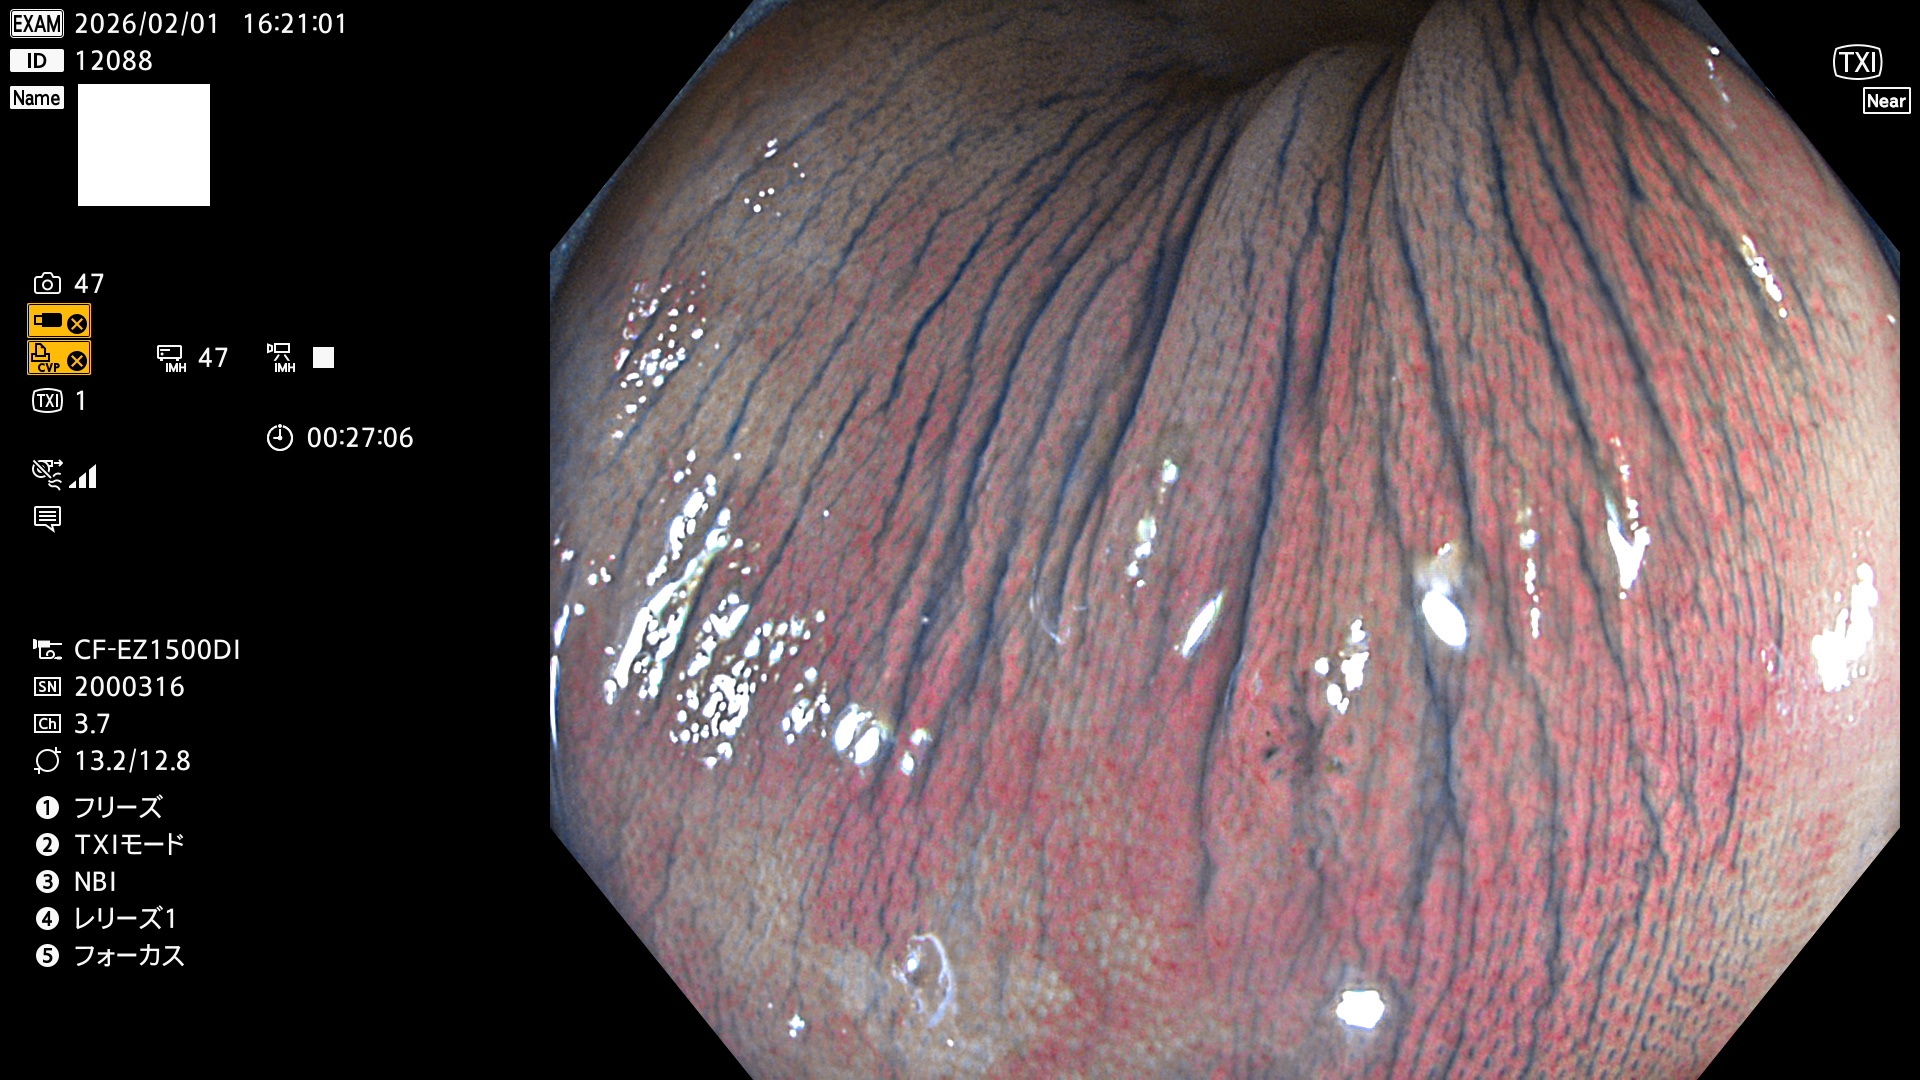

完全に平坦な物をUb、陥凹している物をUcと呼びます。Ubは認識が困難で、Ucはびらん(炎症)と紛らわしいために見落とされやすく、「内視鏡後・大腸癌」の原因になります。

毎週の検査(木・金・土・日)に発見されたUbとUc型・腺腫を、その週の日曜の夜にUPし1週間、提示します。

2026年1月29日〜2月1日の4日間(40件)10個 (Uc_ADR=10個/40人=25%)